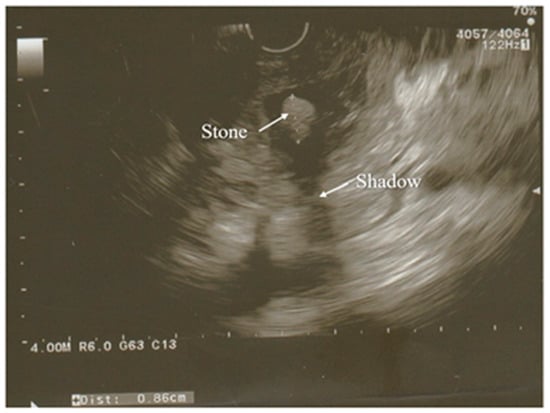

3.3. Ultrasonography

- Sirli, R.; Sporea, I. Ultrasound examination of the normal pancreas. Med. Ultrason. 2010, 12, 62–65. [Google Scholar]

- Rizk, M.K.; Gerke, H. Utility of endoscopic ultrasound in pancreatitis: A review. World J. Gastroenterol. 2007, 13, 6321. [Google Scholar] [CrossRef]

- Kotwal, V.; Talukdar, R.; Levy, M.; Vege, S.S. Role of endoscopic ultrasound during hospitalization for acute pancreatitis. World J. Gastroenterol. 2010, 16, 4888. [Google Scholar] [CrossRef]